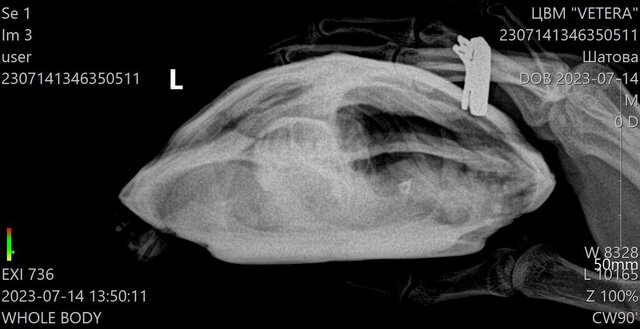

olga@ Ваше имя: Гоша Локация: Тульская область Опубликовано: 14 июля 2023 Автор Опубликовано: 14 июля 2023 (изменено) Рентген сделали в трёх проекциях, видимо мы не так поняли друг друга.Помогите пожалуйста, что нам дальше делать. Изменено 14 июля 2023 пользователем olga@

Консультанты moth Ваше имя: Мария Локация: Москва Опубликовано: 14 июля 2023 Консультанты Опубликовано: 14 июля 2023 @olga@ да, у неё проблемы с одним из лёгких. В норме на этой проекции оба лёгких выглядят как черная пустота (как в исходном примере №3), у Вашей одно лёгкое "мутное" - либо сдулось по какой-то причине, либо жидкость, пневмония и т.п. Здесь уже нужно врачу-герпетологу читать снимок и делать назначения, т.к. у консультантов нет для этого знаний. Это уже не форумный случай. По Туле у нас нет информации о хороших герпетологах, а наш врач, кто курирует форум, сейчас в отпуске на неделю (до понедельника). Могу Вам предложить либо написать её коллеге для онлайн консультации Ганькова Анастасия Сергеевна @Ansergan (ник в телеграмме) либо ещё онлайн консультирует Закружная Анжелика Дмитриевна https://t.me/anzhel_rept, но я не знаю какие у них цены за консультацию. Либо дождаться когда выйдет из отпуска наш врач, для форума у неё цена 300р за весь курс, оплата после консультации, но могут быть задержки в ответах сутки из-за высокой нагрузки. Черепаха сейчас продолжает нормально питаться?